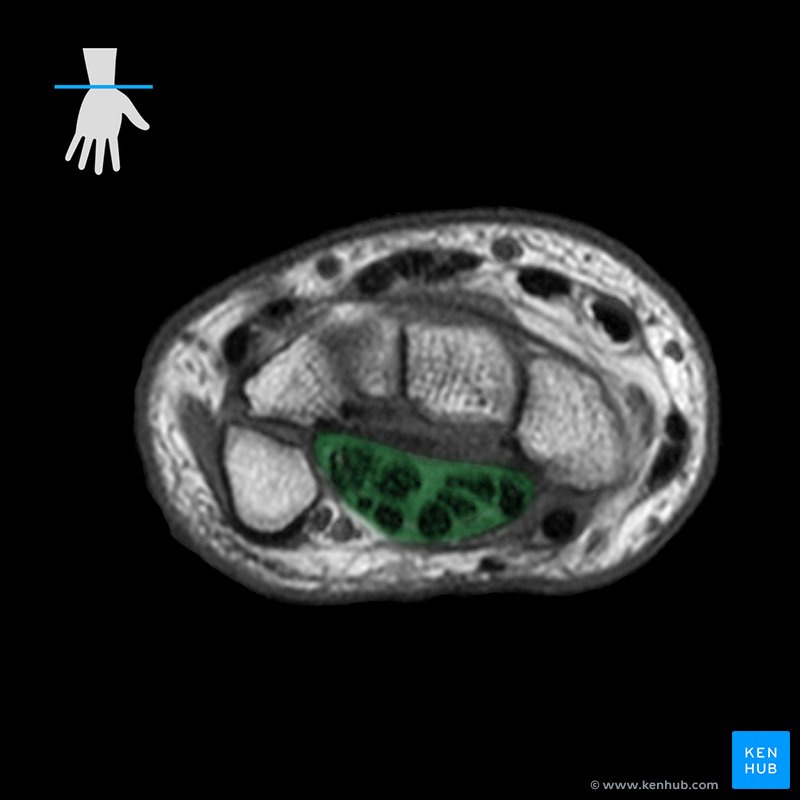

<p>(palms up) (fl.di.sup-is)</p>

(palms up) (fl.di.sup-is)

flexor digitorum superficialis

<p>(palms up) (flex.di.prof)</p>

(palms up) (flex.di.prof)

flexor digitorum profundus